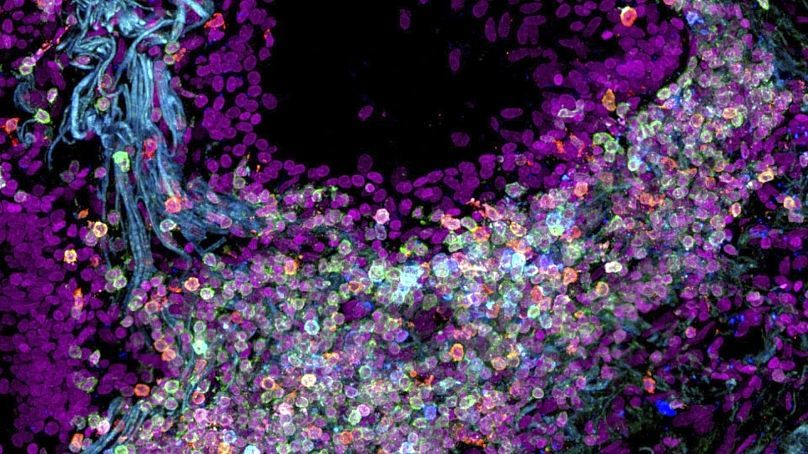

هر نوع سلول نقش خاصی دارد و دانستن این که هر سلول چه ماموریتای دارد میتواند به دانشمندان پشتیبانی کند تا سلامت و بیماریهایی همانند سرطان را بهتر فهمیدن کنند.

دانشمندان در مطالعات خود بر روی برخی از اندامها تمرکز کردهاند، از جمله بازدید ماموریت های سلولها در دهان، معده و رودهها، این چنین سلولهایی که در شکلگیری استخوانها و مفاصل نقش دارند.

به حرف های دکتر تیموتی چان، کارشناس سرطان در کلینیک کلیولند آمریکا، نقشه جاری سلولها نه تنها انواع گوناگون سلولهای انسانی را مشخص می کند، بلکه روابط بین سلولها را نیز اشکار میکند.

دانشمندان در پروژه خود علاوه بر نقش هر سلول، به ربط بین سلولها نیز میپردازند

آقای چان او گفت که این تحقیق به بازدید عمیق زیستشناسی انسان میپردازد و تأثیرات عملی نظیر شناسایی و درمان سلولهای سرطانی خواهد داشت.

او اضافه کرد: «انواع گوناگون سلولها نقاط ضعف خاص خود را دارند. این اطلس، یک جهش بزرگ برای تحقیقات سرطان خواهد می بود.»